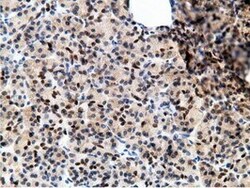

- Immunohistochemical staining of paraffin-embedded human lymphoma tissue using anti-EPM2AIP1 mouse monoclonal antibody. (Heat-induced epitope retrieval by 10mM citric buffer, pH6.0, 100°C for 10min, TA501797)